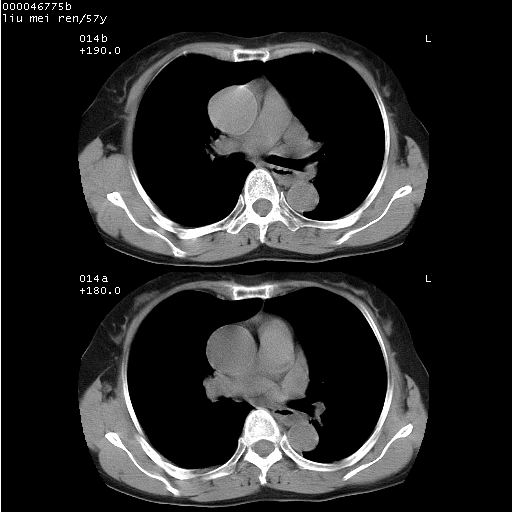

标题: CT12948:鉴赏一下——上腔静脉变异(CT平扫表现)。

患者 女,57岁。因车祸受伤,其家属要求行“全身ct检查”。平素健康。

胸部ct轴位平扫(层厚10mm,螺距1.5,重建间隔10mm),图像如下:

左位上腔静脉,先天变异。

左位上腔静脉,先天变异。与双侧上腔静脉区别。